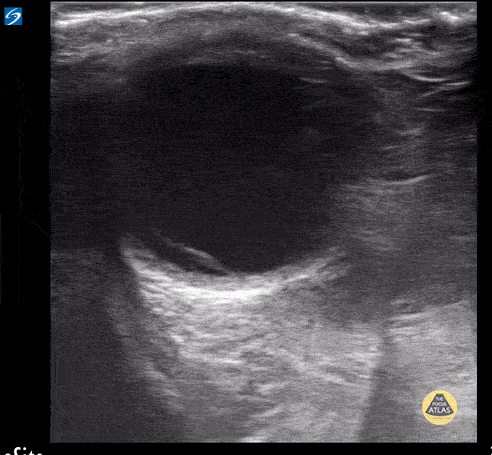

Retinal detachment in a teenager with acute vision loss. Contributor: Peter Gutierrez, MD FAAP FACEP; Children's Healthcare of Atlanta; @pocuspete